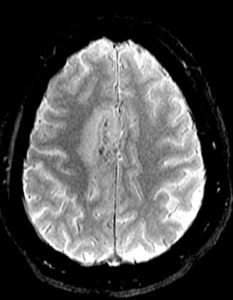

Figure 1A: T2/FLAIR sequence demonstrating right greater than left parasagittal frontal and parietal cortical T2/FLAIR hyperintensity and edema with involvement of the subcortical and deep white matter. There is also incomplete FLAIR suppression of the cerebrospinal fluid in the adjacent sulci, indicative of an inflammatory process. (Click to enlarge.)

Magnetic resonance imaging (MRI) of her brain revealed a right parasagittal T2/FLAIR, and cortical and subcortical white matter hyperintensity with gyral enhancement concerning for primary or metastatic malignant disease.